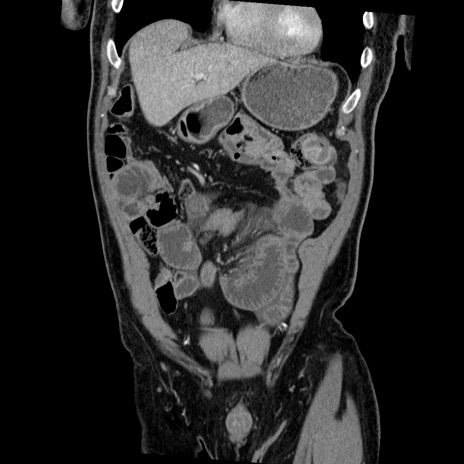

横断像

【症例】50歳代男性

【主訴】腹痛

【現病歴】AVMからの被殻出血のため回復期リハ病棟入院中。 本日午後3時頃急に下腹部痛が出現した。

【既往歴】AVM、被殻出血、虫垂炎、高血圧

【身体所見】意識晴明、左半身不全麻痺、会話の理解は良好、36.5°C、腹部:膨隆、全体に板状硬、下腹部正中に圧痛点あり、反跳痛-、筋性防御不明、右下腹部にope scar

【データ】WBC 9400、CRP 0.06